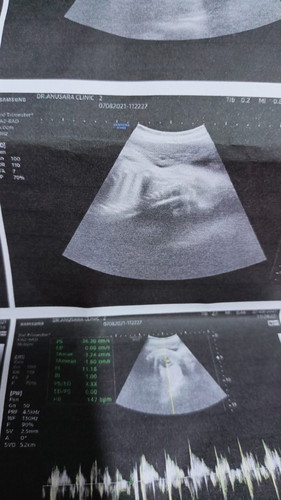

33+5w.ขอดูภาพอัลตร้าซาวด์แม่ๆหน่อยค่ะ

ไปซาวด์มาน้องนอนอยุ่ในท่าตะแครง ลักษณะหัวน้องแบบนี้ยาวไปมั้ยคะ หรือปกติ

ซาวตอน16wค่ะตอนนี้กังวลมากค่ะเพราะหมอโทรมาบอกว่าน้องมีความเสี่ยงเป็นดาวน์ซินโดรม1ใน1000คนวันที่27นี้หมอนัดไปเจาะน้ำคร่ำแล้วค่ะ😥